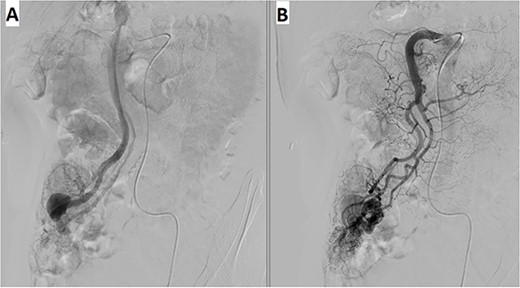

A 57-year-old male patient with a history of hypertension was referred to our hospital for multiple episodes of painless bloody stools for 2 weeks. No gastrointestinal symptoms were observed, such as abdominal pain, nausea or vomiting. A digital rectal examination showed bright red blood. On admission, laboratory evaluation revealed mild anemia with hemoglobin of 103 g/dL. Other than that, there were no other abnormalities. Lower and upper gastrointestinal endoscopy was performed, but the cause of the bleeding could not be identified. Due to the signs and symptoms of ongoing bleeding, we decided to perform imaging tests to make a diagnosis. Abdominal contrast-enhanced computed tomography (CT) revealed a thickened appendix (17 mm in diameter and wall thickening 6.4 mm) without signs of inflammation and images of vascular proliferation and dilated vein around the appendix (Fig. 1). An angiography was performed and demonstrated the AVM of the appendicular artery and vein (Fig. 2).

Angiography revealed (A) vascular tangle with (B) early venous filling in the appendicular artery and vein.

AVM in the mesoappendix is a very rare clinical entity and has been reported by some authors where AVM is the etiology of appendicitis [12, 13]. Contrast-enhanced CT and angiography are good choices for looking for vascular malformation. CT scan with IV contrast not only helps to identify vascular lesions but also helps to rule out other bowel wall lesions. Mesenteric angiography is effective in diagnosis as well as intervention. However, the appendicular artery angiographic interventions were relatively contraindicated because of the high risk of ischemia of the appendix and appendicitis [14]. For that reason, surgical resection is considered as the standard of management. Intraoperatively, this is important to identify and remove all AVM lesions to avoid new lesions that may develop after incomplete resection [15]. In this case, we performed a laparoscopic appendectomy; during the operation, we also dissected the appendicular vein up to the level of the superior mesenteric vein to rule out any other AVM.